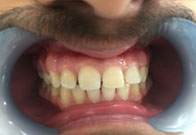

(4) Diastema Closure

Before Treatment

After Treatment

Patient with a complaint of a gap in between upper central incisors. Dental Veneers done to close the gap between the central incisors